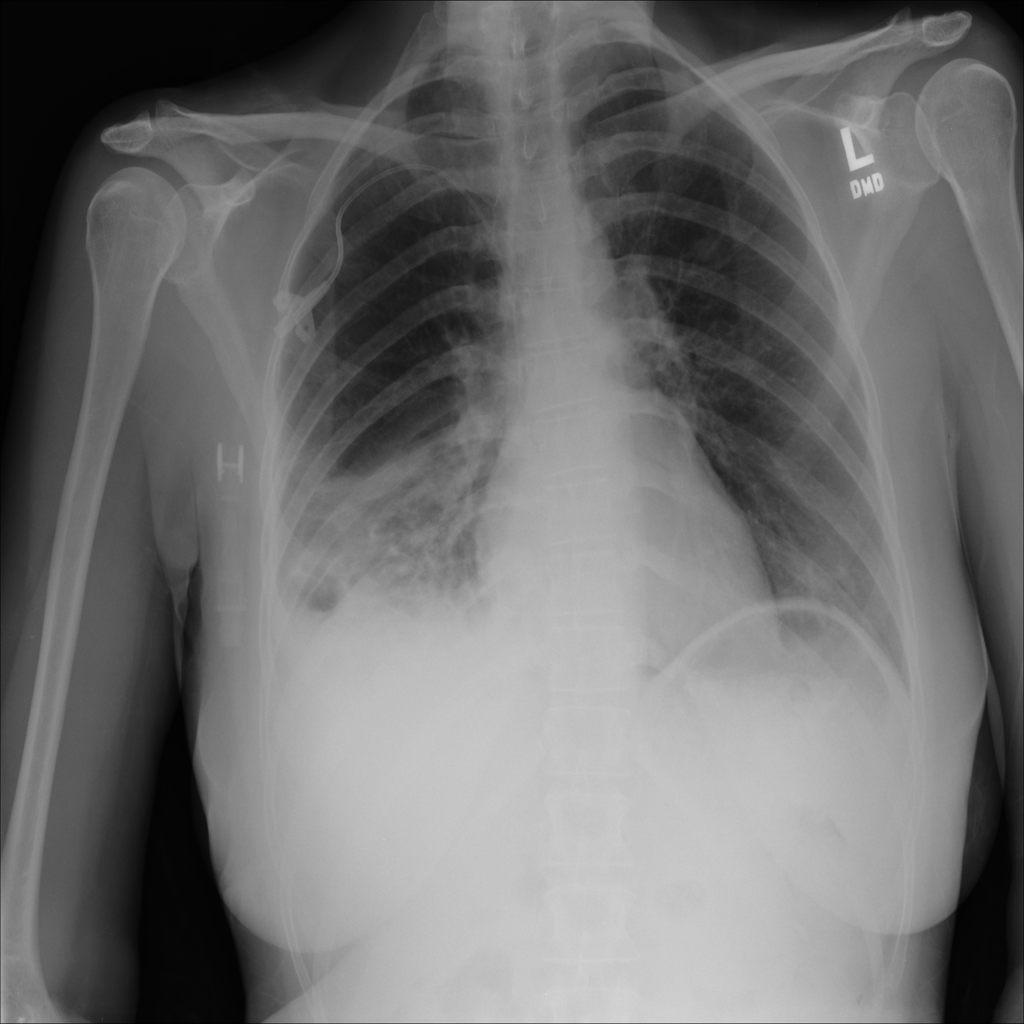

Showing up to 90 reference images for Pneumothorax.

PAT-4639 · IMG-011Pneumothorax

PAT-4639 · IMG-011

AP